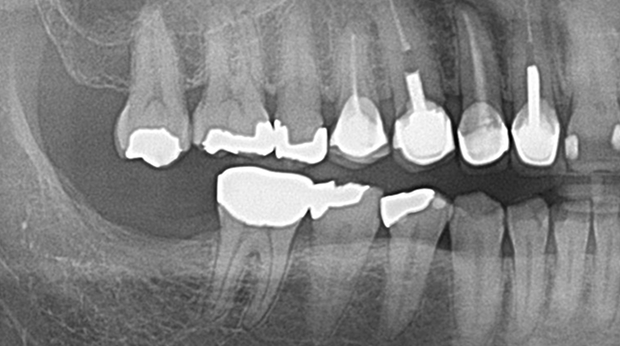

매복 사랑니 발치

의식하진정법(수면마취)/임플란트

고난도 수술 진료

임플란트와 사랑니 발치는 외과적 시술로 잇몸을 절개하는 외과적 시술은

짧으면 짧을 수록 시술 후 붓기와 통증이 최소화됩니다.